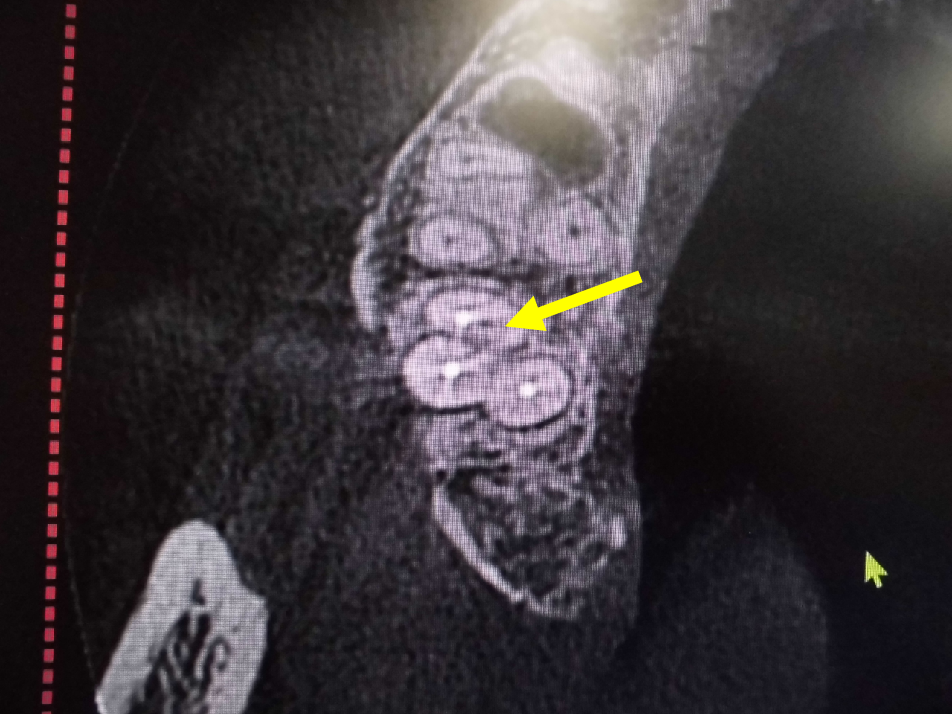

左上奥歯が割れています。一般的なレントゲンではわかりません。

CTでは破折線がはっきり見えます。患者様も納得しやすいです。